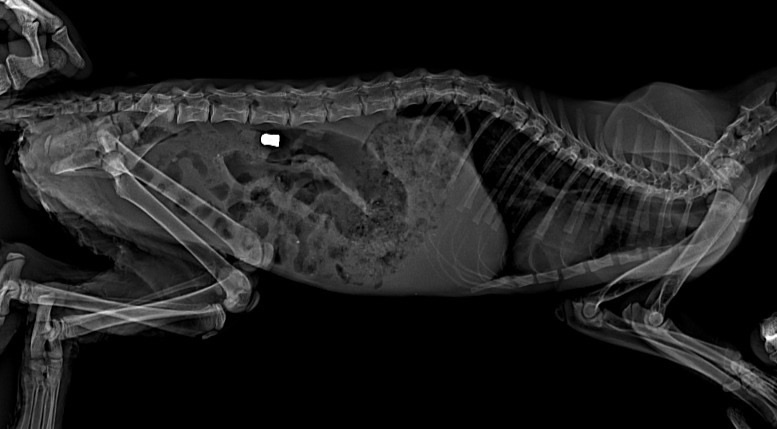

Перелом таза и ПУЛЯ в брюшке малюсенького котеночка!

Сколько к нам поступало животных с пулями, не представляете. Котёнок тоже поступил в один день с щенком и у обоих ПУЛЯ! У кого поднимается рука стрелять в малышей, даже представить страшно… Получится ли в этот раз помочь, не известно. Но, точно знаем, что если ничего не делать, это верная смерть БЕЗ ШАНСА, даже малейшего…

У малыша отсутствует чувствительность задних конечностей, некроз в паховой области. Естественно котёнок ходит в туалет по-большому и по-маленькому самопроизвольно. В связи с этим очень нужны пеленки 60*90 https://www.wildberries.ru/catalog/486716355/detail.aspx ! Так же у нас хватило денег только на рентгены 2 шт, капельницы ставим. Но, этого НЕ достаточно. Нужно сдать ПЦР (3 000 руб), так как если у котёнка вирусная инфекция, шансов практически не остается и само лечение необходимо другое.